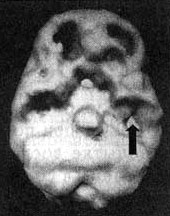

Выступая в качестве судебного психиатра-консультанта, я согласился с клиническим диагнозом СДВ, а на основании постоянной агрессивности Брэдли и нарушений на ЭЭГ заподозрил и дисфункцию левой височной доли. Я назначил ему сканирование SPECT при попытке сосредоточиться без лекарства и попытке сосредоточиться с Ritalin. Результаты сканирования в состоянии покоя выявили умеренное снижение активности левой части префронтальной коры и левой височной доли. При попытке сосредоточиться наблюдалось выраженное угнетение функции префронтальной коры (характерное нарушение при СДВ) и обеих височных долей. Третье сканирование мы провели через час после того, как Брэдли принял 15 мг Ritalin. На этот раз мы увидели выраженную активизацию префронтальной коры и обеих височных долей, хотя в левой височной доле небольшое снижение активности все еще сохранялось. Мозг Брэдли Трехмерное изображение поверхности, вид снизу. ![]() Снимок мозга при попытке Брэдли сосредоточиться (без лекарственного препарата); обратите внимание на снижение активности в левой префронтальной коре и левой височной доле (стрелка). ![]() Снимок мозга при попытке сконцентрироваться (на фоне приема риталина). Обратите внимание на общее улучшение активности. Стало ясно, что само состояние мозга Брэдли создавало предпосылки для возникновения длительных проблем и с поведением, и с учебой. То, что он употреблял наркотические вещества, сильнее угнетало и без того сниженную функцию префронтальной коры и височных долей, снижая исполнительные функции и запуская агрессивные тенденции. Вполне вероятно, что, если бы раньше Брэдли объяснили его главную проблему и оказали необходимую психотерапевтическую помощь, связанную с его нежеланием принимать лекарство, его преступление можно было бы предотвратить. В тюрьме ему назначили Cylert (препарат, как и Ritalin, стимулирующий мозговую деятельность) и Depakote. За последние два года у него не было ни одной вспышки ярости. 3. Наркотики или алкоголь могут использоваться пациентами в качестве средства, помогающего им справиться с нарушением мозговой деятельности, провоцирующим агрессию. У многих наркоманов бывает не один, а несколько психиатрических диагнозов. Мы полагаем, что они употребляют наркотические вещества, чтобы справиться с проявлениями таких психиатрических или неврологических нарушений, как депрессия, паника, тревожность, связанная с посттравматическим стрессом и даже с агрессивным поведением. Расти Расти (28 лет) привели ко мне на прием его родители. У него развилась тяжелая зависимость от метамфетамина, из-за которой вся его жизнь пошла прахом. Он был не в состоянии спокойно работать, бил свою девушку (четыре раза его арестовывали за нападение и избиение), плохо обращался со своими родителями, хотя они пытались ему помочь. Он пять раз лечился от наркотической зависимости и пять раз прерывал лечение. В последний раз психолог посоветовал родителям Расти проявить по отношению к их сыну жесткую позицию: пускай тот «ударится» так, что сам попросит о помощи. Однако родители читали о моей работе и решили сначала прибегнуть еще к одному средству: отвести своего сына ко мне. Сам факт, что Расти не поддавался лечению традиционными методами, заставил меня заподозрить у него нарушение мозговой деятельности. Мы с родителями наметили дату проведения сканирования, однако сам Расти ничего не знал до того самого дня, на который было намечено обследование. В клинику он явился еще «под кайфом» от большой дозы метамфетамина, которую он принял накануне вечером. Расти рассказал мне, что принял наркотик. «Мне очень неловко, что я сорвал обследование, — сказал он. — Я приду на следующей неделе. Обещаю, что ничего принимать не буду». Раньше мне часто хотелось сделать сканирование, когда пациент находился под воздействием наркотического вещества, чтобы посмотреть, как оно воздействует на мозг, но я не делал этого по этическим соображениям. Однако когда пациент являлся на обследование, находясь под действием наркотика, этические соображения были уже ни при чем. Я решил провести Расти первое сканирование, пока эффект от приема метамфетамина еще сохранялся, а второе — через неделю, когда он уже не будет находиться под действием наркотиков. Это решение оказалось весьма правильным. Когда Расти находился под воздействием высокой дозы метамфетамина, активность мозга у него выглядела подавленной. Неделю спустя, когда он пришел на сканирование, не принимая никаких наркотиков, оказалось, что у Расти очень сильно повышена активность левой височной доли, что, скорее всего, и было причиной его агрессивного поведения. Судя по всему, Расти бессознательно занимался самолечением, снижая активность «перегретой» левой височной доли с помощью высоких доз метамфетамина. Тогда я стал настойчивее пытаться выяснить, не было ли у Расти прежде травм головы. Сначала ни он, ни его родители ни о какой травме не помнили. Однако затем Расти вспомнил, что во втором классе он с разбегу ударился о шест, на котором был закреплен баскетбольный щит, и на какое-то время потерял сознание. Это и могло стать причиной нарушений в левой височной доле. Тогда я назначил Расти Tegretol (противосудорожный препарат, стабилизирующий активность височных долей). Через две недели состояние Расти стало таким, каким оно не было на протяжении нескольких лет. Он успокоился, мог контролировать свое настроение и впервые удержался на работе, где ему хорошо платили. Дополнительным преимуществом обследования Расти стала возможность наглядно показать ему, какой вред он наносил собственному мозгу, употребляя метамфетамин. Даже при том, что наркотик помогал справляться с нарушением в работе височных долей, он тем не менее отравлял его мозг. Как это бывает и у других наркоманов, у Расти по всей поверхности мозга были видны «дыры» — очаги отсутствовавшей активности. Созерцание этой картины стало для него еще одним стимулом отказаться от наркотиков и заняться правильным лечением существовавших у него нарушений. Таким образом, SPECT, с одной стороны, сыграл роль эффективного метода диагностики, позволившего точнее выявить главную причину проблем у Расти. С другой стороны, SPECT стал действенным терапевтическим методом, позволившим преодолеть сопротивление Расти. Одна картинка стоит тысячи убеждений. Часто информация, которую мы получаем с помощью методики SPECT, является решающей, чтобы убедить пациента оставить пагубное пристрастие. Мне хотелось бы знать, сколько еще людей, чьи пристрастия не поддаются обычному лечению, продолжают, сами того не подозревая, пытаться таким образом справиться с каким-то нарушением, от которого проистекают все их трудности. При этом и семья, и общество считают их безвольными и морально ущербными. «Жесткая позиция» по отношению к Расти не решила бы его проблемы. Расти ![]() Трехмерное изображение поверхности — вид сбоку. После того, как Расти употребил большую дозу метамфетамина, левая височная доля его мозга выглядит сравнительно нормально. |